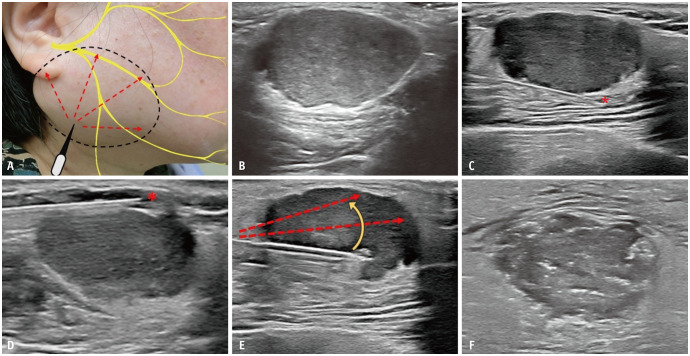

Objective: To retrospectively compare the safety and efficacy of ultrasound-guided radiofrequency ablation (RFA) with parotidectomy for superficial pleomorphic adenoma (PA).

Materials and methods: From March 2022 to October 2023, 88 patients diagnosed with superficial parotid PA underwent either RFA (n = 12; mean age, 47.1 years) or parotidectomy (n = 76; mean age, 47.8 years). Patients in the RFA group were matched to those in the surgery group in a 1:1 ratio using propensity scores based on age, sex, tumor volume, diameter, location, and comorbidities. Ultrasound characteristics, cosmetic scores (0-4), numerical rating scale scores (0-10), and complications were assessed before the procedures and at 1-, 3-, and 6-month follow-ups. Outcomes were compared between baseline and follow-up in the RFA group and between the RFA and surgery groups.

Results: In the RFA group, significant reductions in tumor volume were observed between baseline (median, 2.02 cm³) and the 1-month follow-up (median, 1.21 cm³; P = 0.015), between the 1-month and 3-month follow-ups (median, 0.53 cm³; P = 0.002), and between the 3- and 6-month follow-ups (median, 0.23 cm³; P = 0.003). The volume reduction ratios at 1, 3, and 6 months were 39.7%, 79.9%, and 88.0%, respectively. The cosmetic score was significantly lower at 3- and 6-month follow-up compared to baseline (median 1 and 1 vs. 4, P = 0.04). The numerical rating scale scores did not differ significantly from baseline throughout follow-up. In the propensity score-matched analysis (12 patients per group), RFA was associated with a shorter median procedure time (61.5 vs. 253.3 minutes; P < 0.001), shorter hospital stay (0 vs. 4 days; P < 0.001), and lower cost (1859.9 vs. 3512.4 USD; P < 0.001) than parotidectomy, with no significant difference in overall complication rates (33.3% [4/12] vs. 41.7% [5/12]; P = 1.000).

Conclusion: RFA may be a safe and effective alternative to surgery for superficial parotid PA, offering a shorter median procedure time, shorter hospital stay, and lower costs.